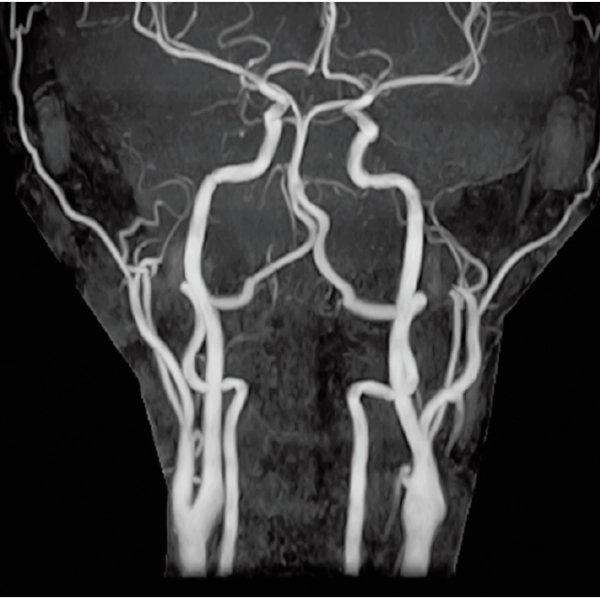

3DTOF MRA (MIP), 1:26

3DTOF MRA RADAR (MIP)

3D MRCPA (MIP)

Lower extremity

non-contrast MRA (MIP)